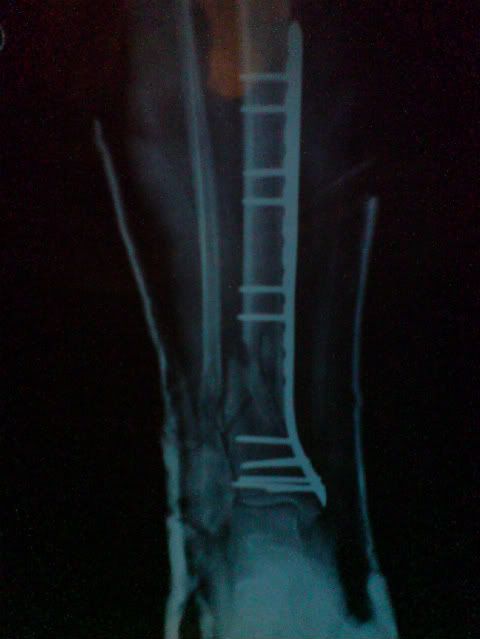

Two weeks after the accident I got x-rays to take to my orthopaedic surgeon.

Left - view from the front. Right - view from the side, but reversed because I'm a dork.

Closeup of the fracture. If you're cringing or shocked, that's normal. I suddenly understood why the guy taking my x-rays in the hospital had winced and told me I had an impressive break. I was pretty quiet coming out of the x-ray place. To give you a sense of scale, the plate is about 2/3 the length of my tibia. In total I have seen 12 screws - 6 are clustered at the base and may look like 5, one mostly obscures the other at that angle.

I took those to my orthopaedic surgeon so he could see my progress and get me a fibreglass cast. Instead, he cut my plaster cast off, took my stitches out (22 stitches! Never had any before this), and sent me off bare-legged. I was pretty surprised (so was everyone else) and it was scary at first to have my leg so bare and exposed to anything bad that could happen. I ended up liking the freedom, though, because it meant my leg wasn't so heavy and I could do things more easily.